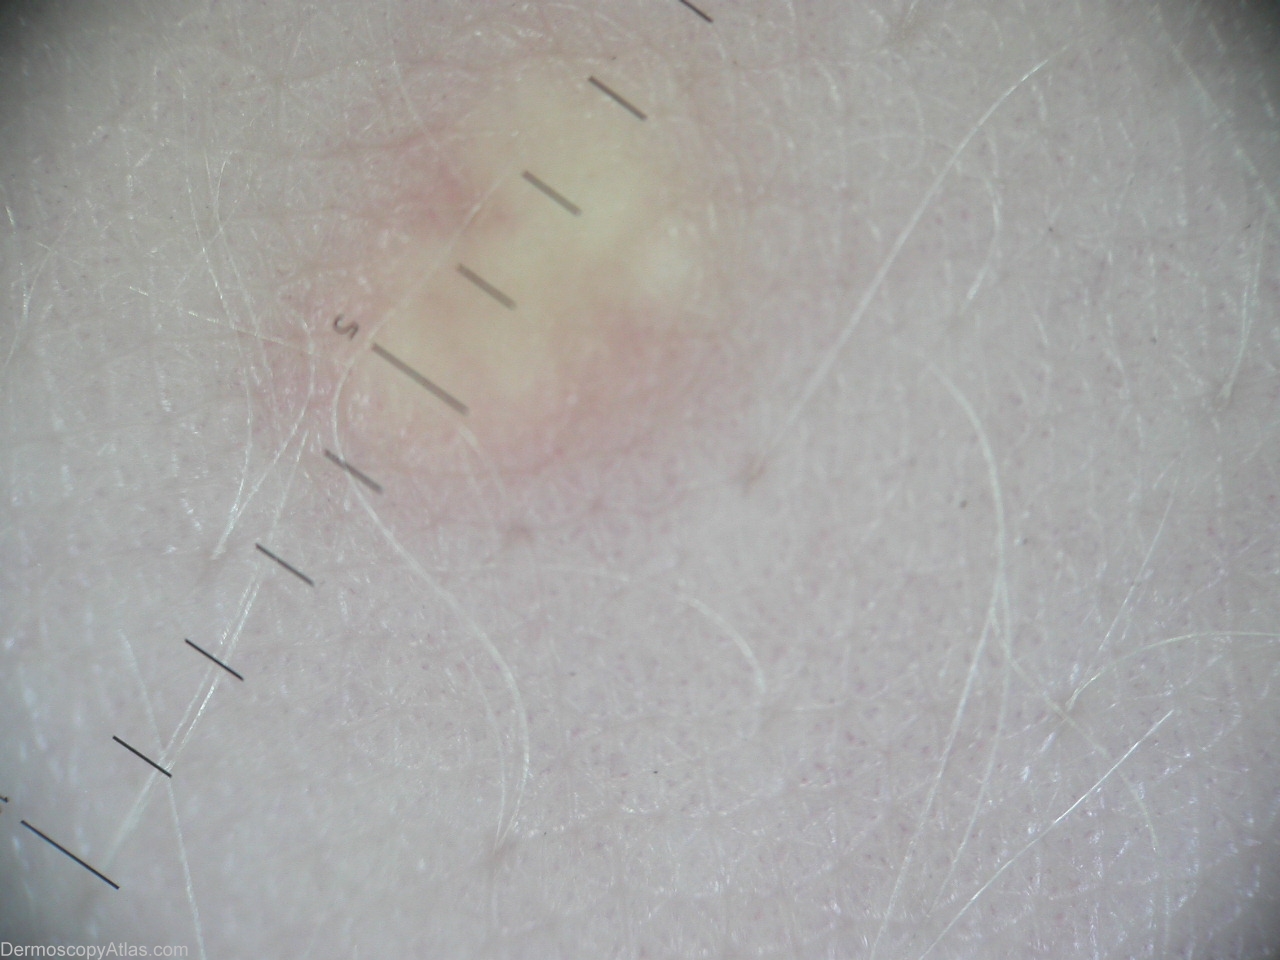

Diagnosis - Eruptive xanthoma

Diagnosis: Eruptive xanthoma